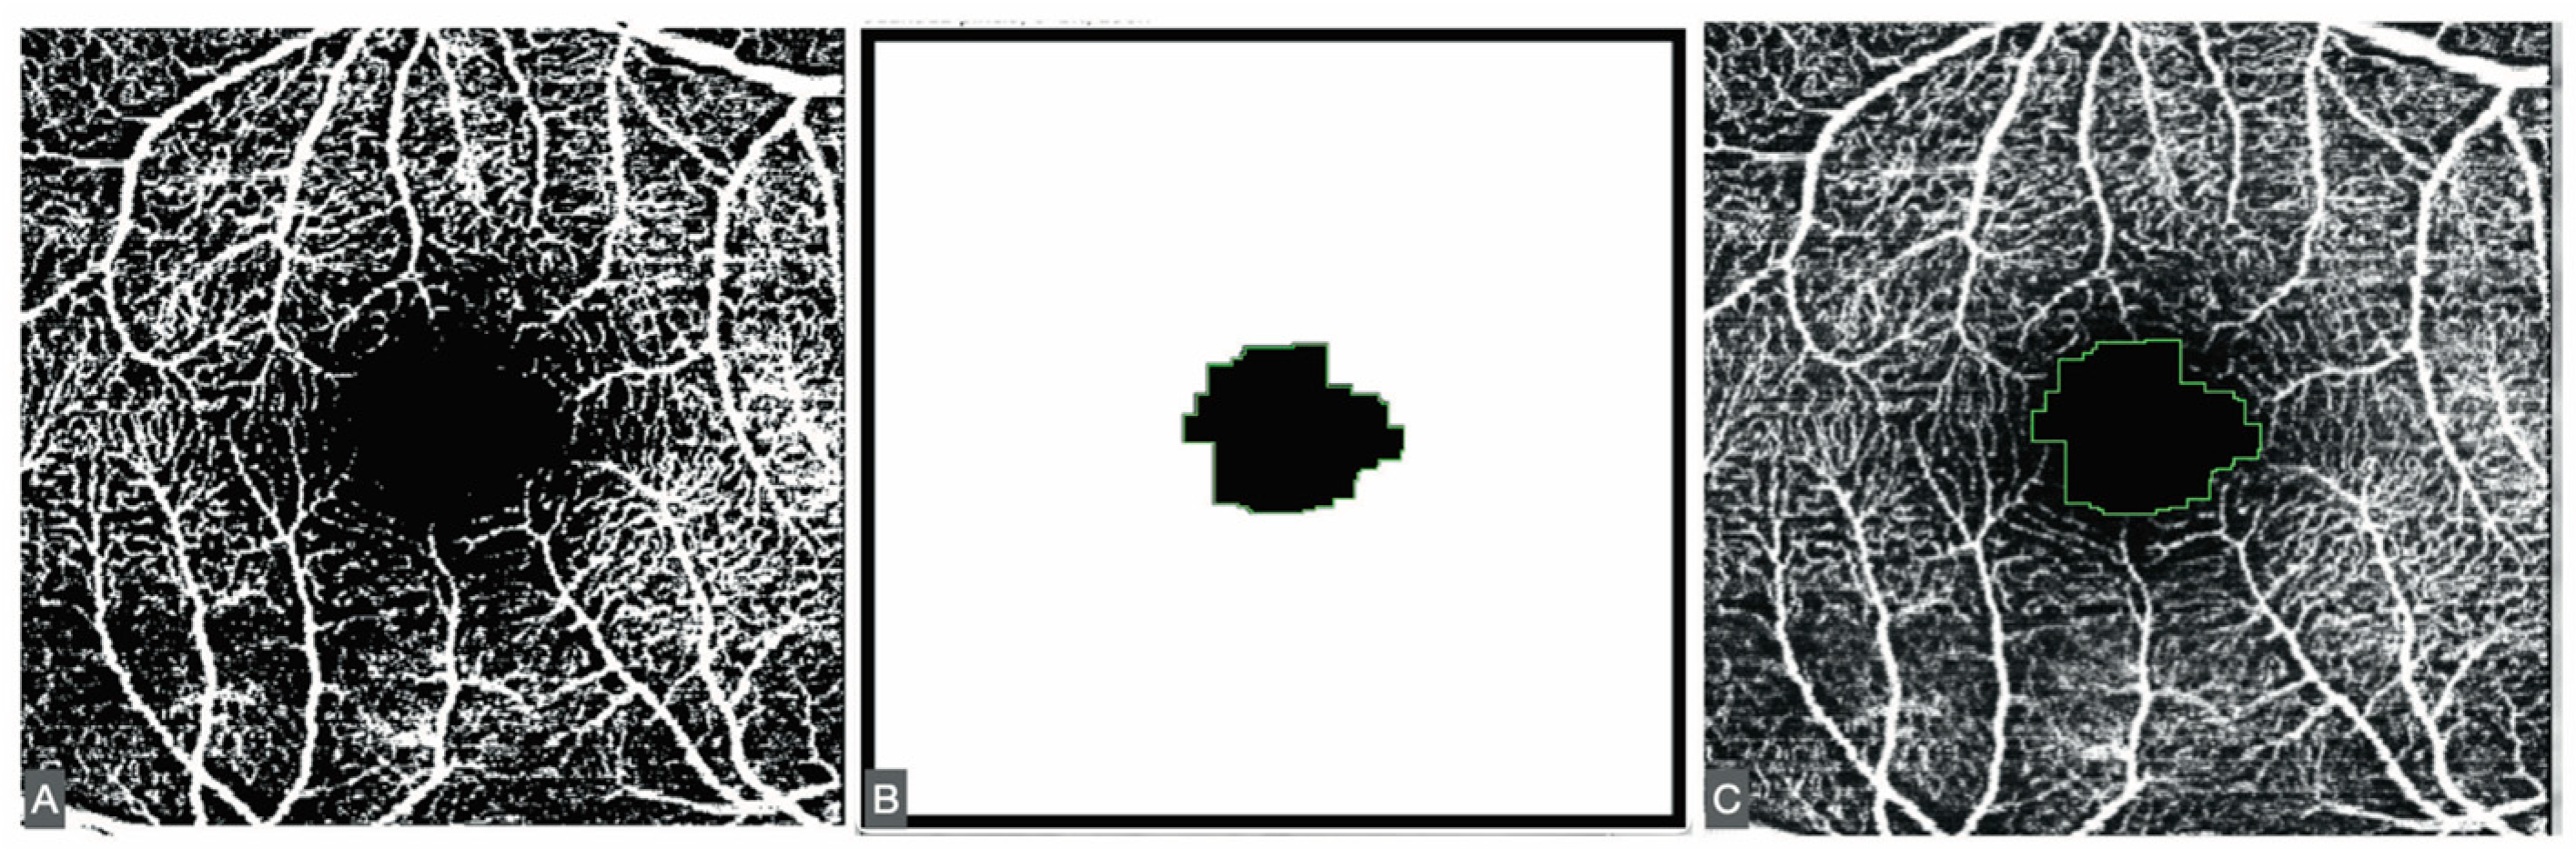

The FAZ was measured using a script adapted from Ishii [11]. Minor modifications were introduced, including adjustment of image size and the application of Otsu binarization [12], a local/global thresholding method that reduces artifacts compared with other binarization algorithms (Figure 1).

Figure 1. (A) Otsu binarization of the SVP. (B) The results of the ImageJ script. (C) Fit of the result of the script in the 8-bit former image.